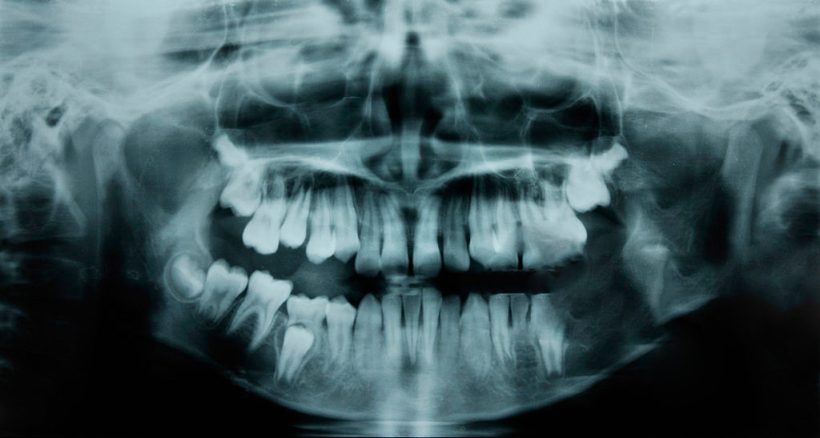

GOODBYE, FILLINGS Dental fillings may soon be left in the ash heap of history, thanks […]

Source: Scientists Have Discovered a Drug That Fixes Cavities and Regrows Teeth